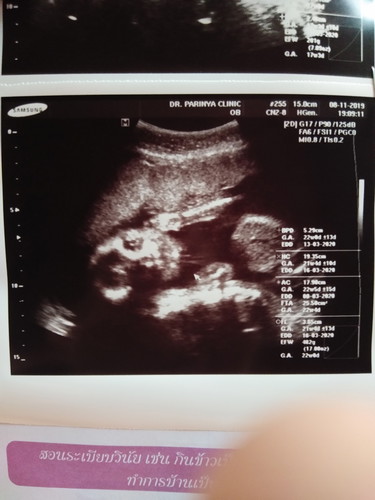

ตัวย่อ FTA ในใบซาวคืออะไร ใครรู้บ้างคะ